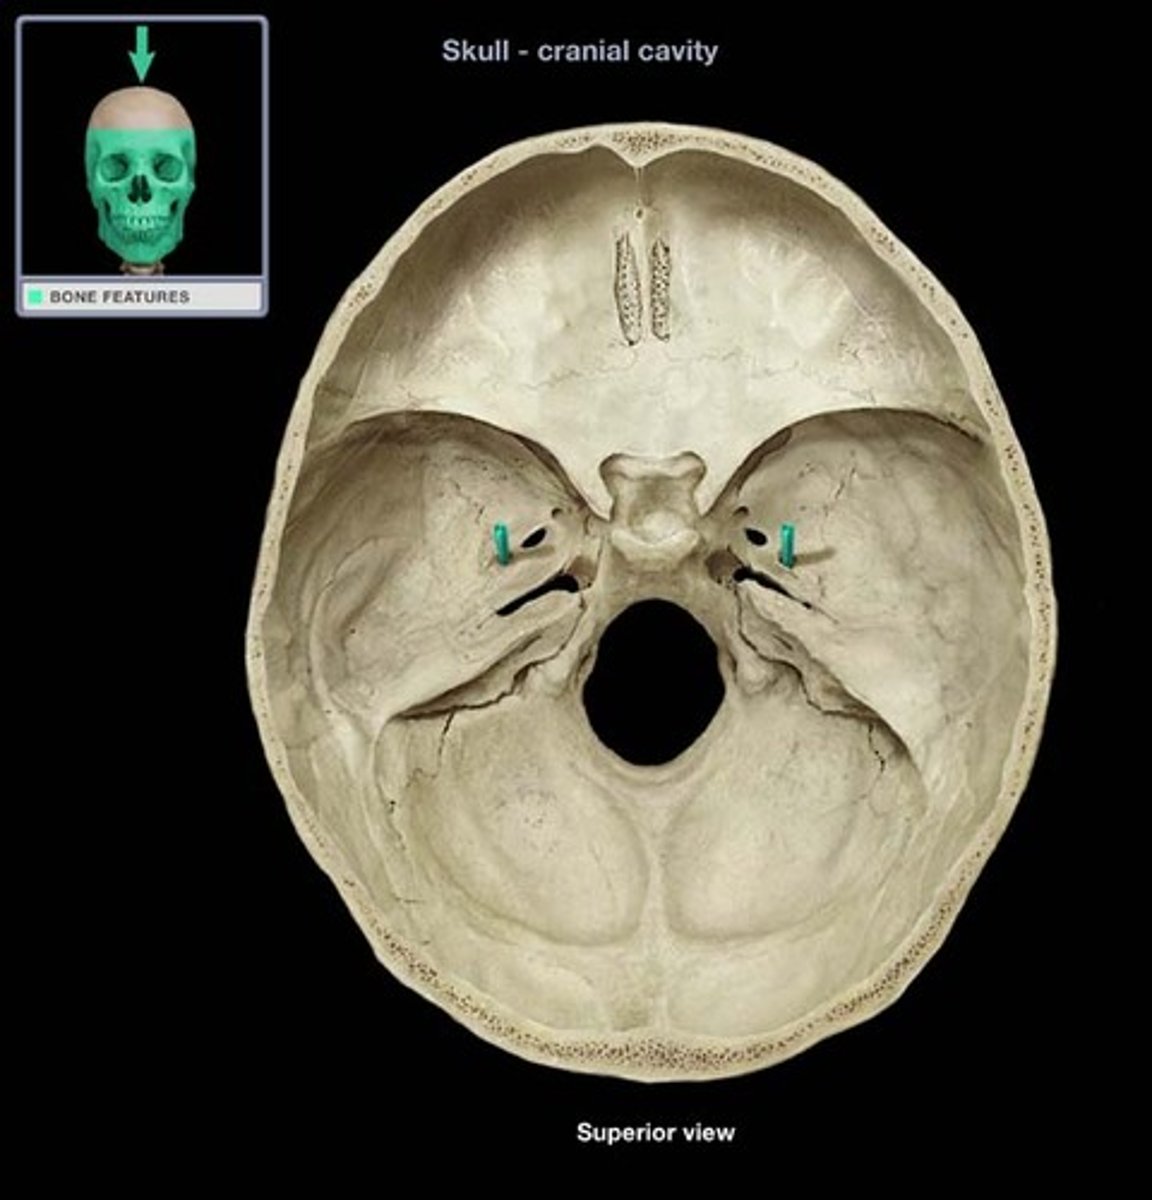

optic canal

hole that transmits the optic nerve (CN II) & the opthalmic artery

superior orbital fissure

opening that transmits cranial nerves III, IV, V1 and VI, and the superior opthalmic vein

foramen rotundum

hole that transmits the maxillary nerve (CN V2)

foramen ovale

hole that transmits the mandibular nerve (CN V3) and the accessory meningeal artery

foramen spinosum

hole that transmits the middle meningeal artery and vein

internal acoustic meatus

passage for facial (VII) and vestibulocochlear (CN VIII) nerves

jugular foramen

opening that transmits the internal jugular vein and cranial nerves IX, X, and XI

hypoglossal canal

hole that transmits the hypoglossal nerve (CN XII)